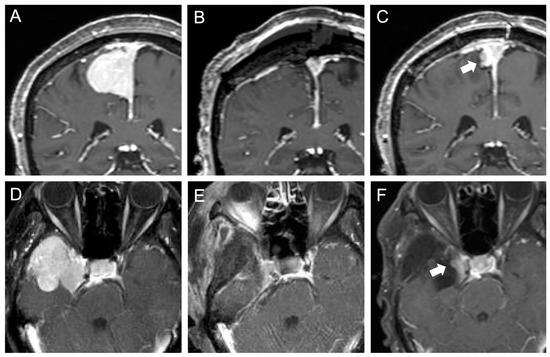

3.2. Early Postoperative MRI Findings and Risk Factors for Postoperative Infarction

3.3. Late Postoperative MRI Findings and Risk Factors for Early Recurrence

4.2. Role of Early Postoperative MRI to Detect Ischemia after Meningioma Resection

4.3. Role of Early Postoperative MRI to Evaluate Recurrence of Meningiomas